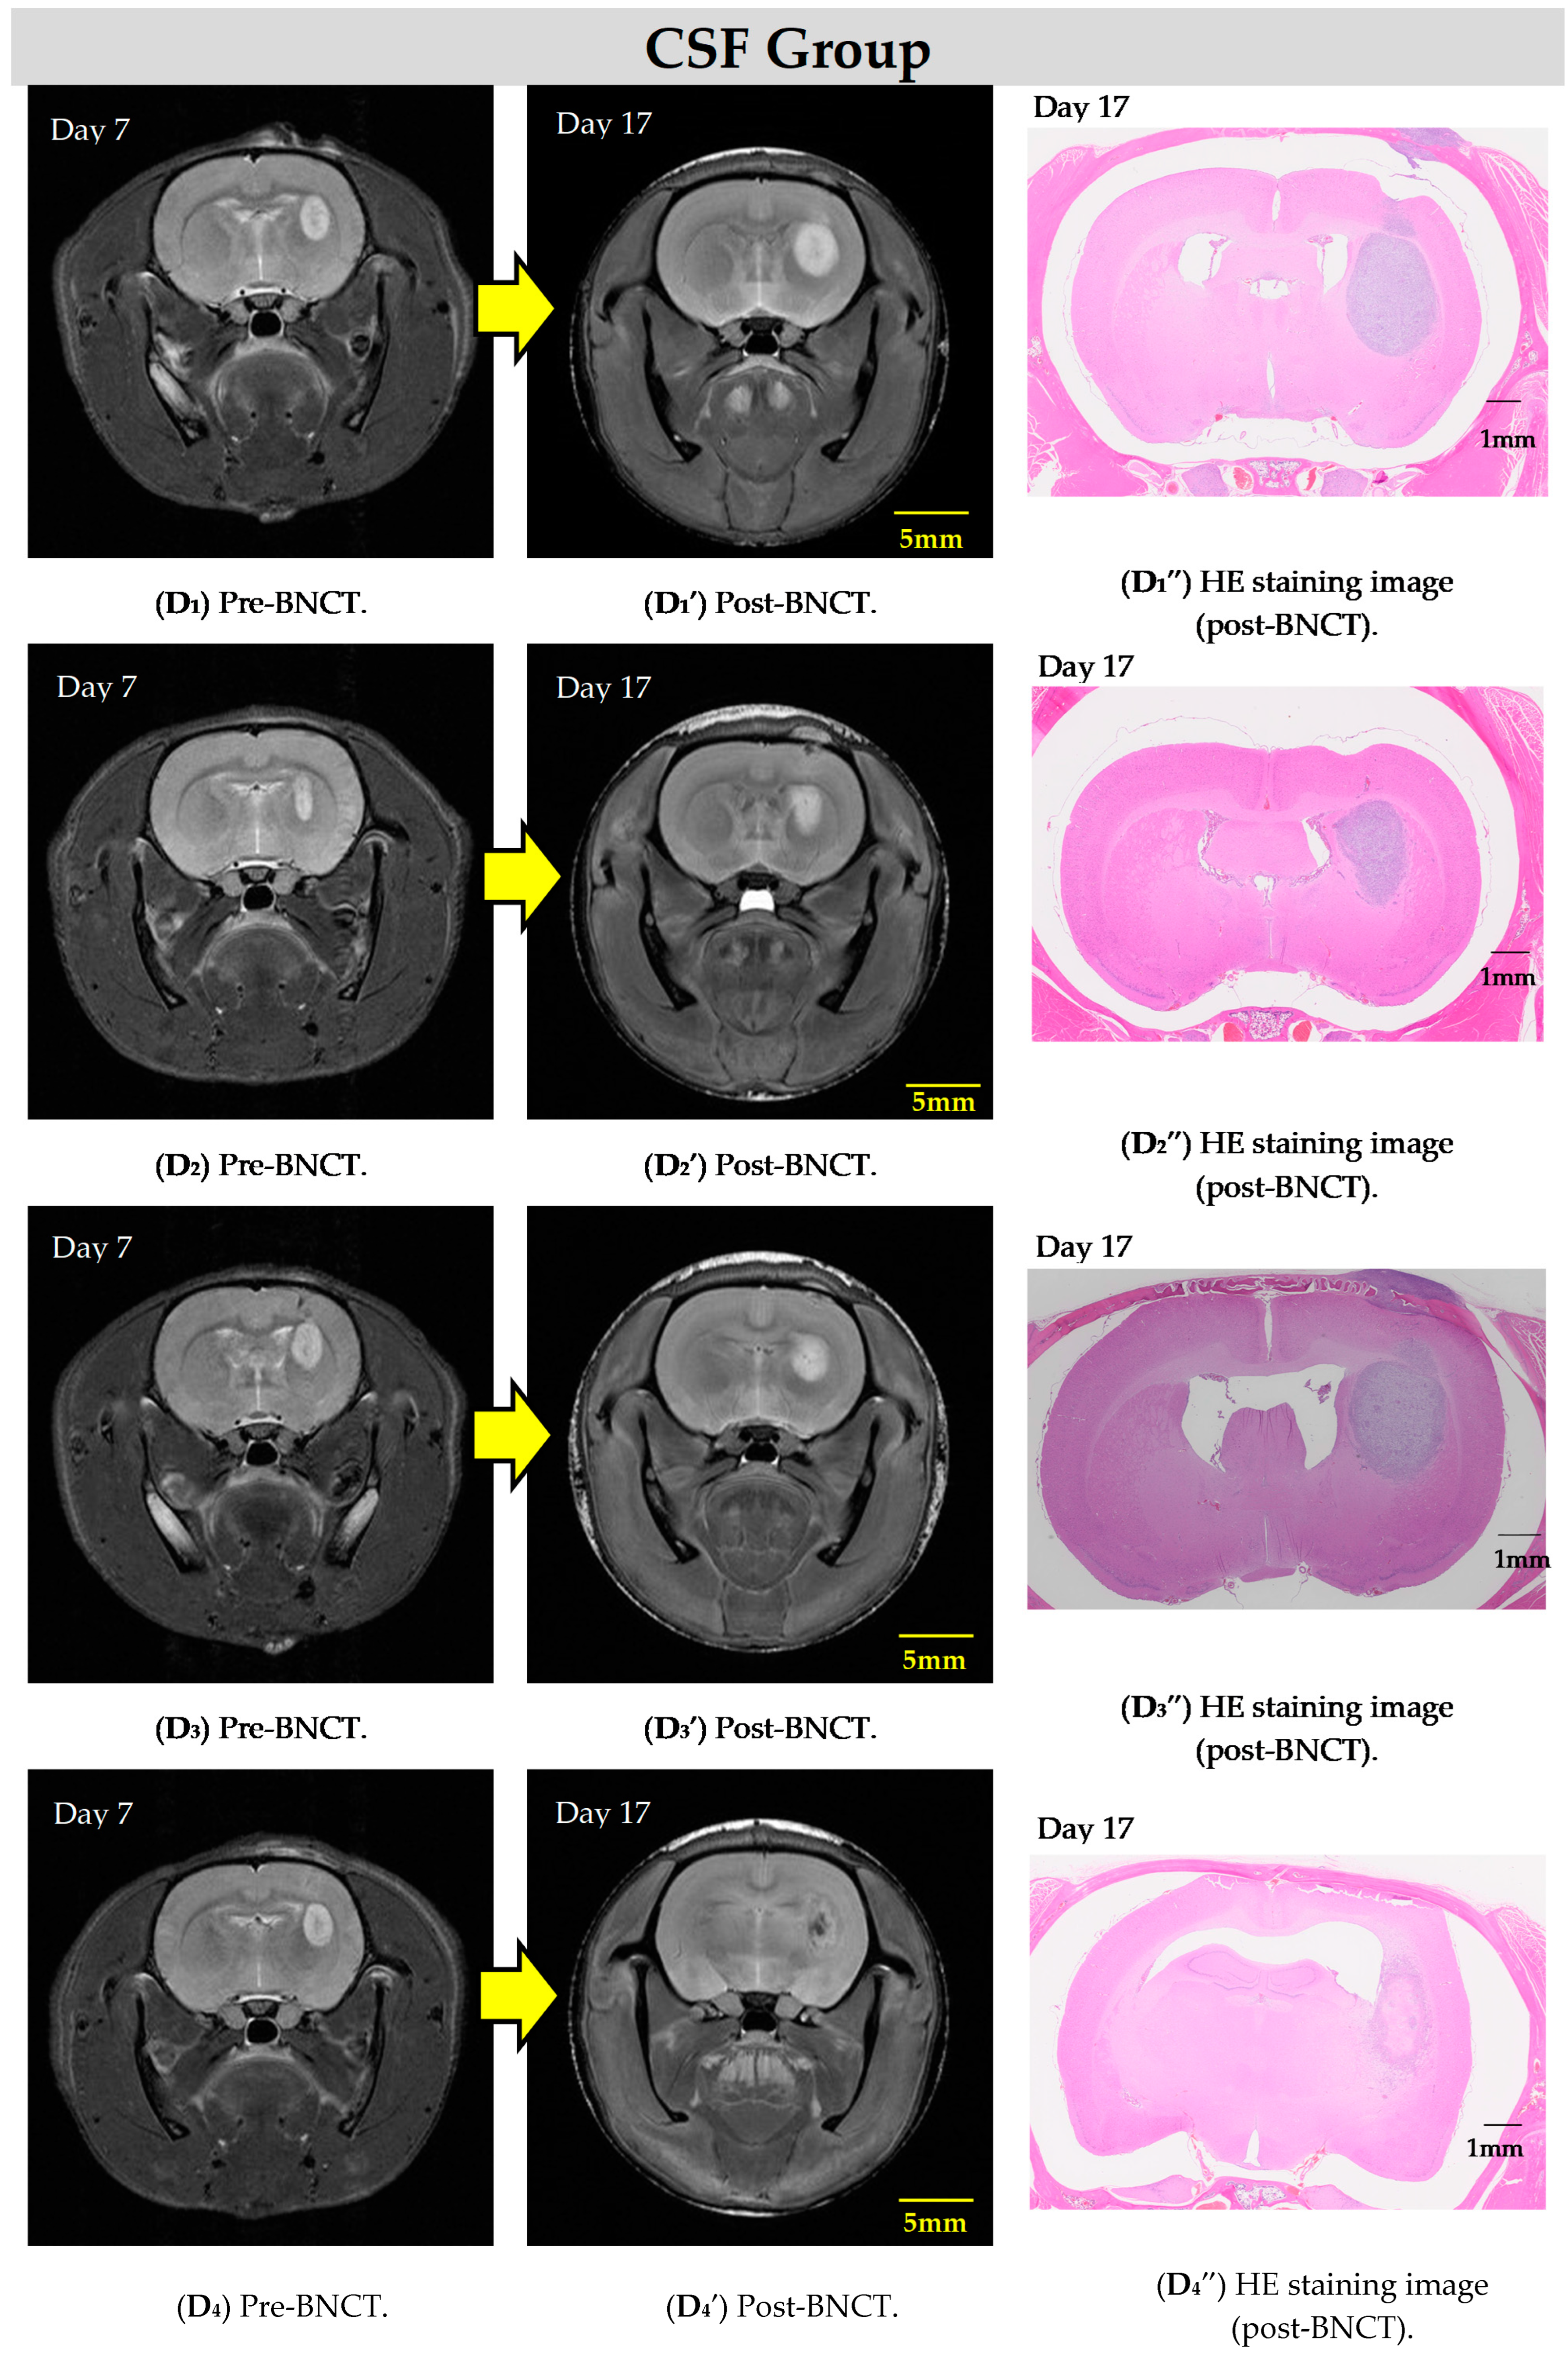

2.2. BNCT Effect on the CSF Administration Method of 10BPA

2.3. Pre- and Post-Treatment MRI Assessment

2.4. Hematoxylin and Eosin Staining of C6 Rat Glioma Brain Sections

| Day 0 * | Day 7 | Day 10 | Day 17 | |||

|---|---|---|---|---|---|---|

| C6 Cell Transplantation | MRI (Pre-BNCT) | BNCT | MRI (Post-BNCT) | HE Staining | ||

| BPA | Irradiation | |||||

| CSF group | 〇 | D | 16 mg/kg | 20 min | D′ | D″ |